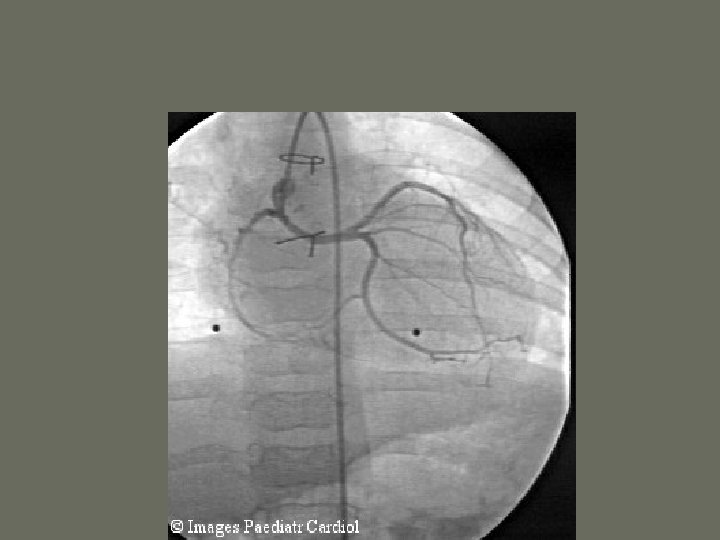

Cardiac Catheterization • one of the most common angiographic procedures performed in the US • may be performed as a cardiac ________ or angiocardiography • includes ________measurements • performed for a wide variety of problems dealing with the heart • Blood Supply to the Heart • Pulmonary Circulation

Cardiac Catheterization

Cardiac Catheterization • Angiocardiography 1. radiographic evaluation of the _______ of the heart and various valves 2. hemodynamic monitoring is the evaluation and recording of the function of the heart 3. include oxygen saturation, pressure tracings, and cardiac _______